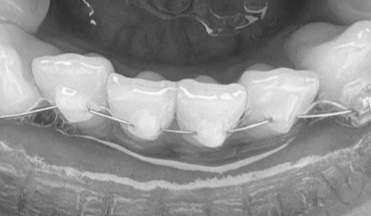

교정일기7. 가위교합 하악 바이트 플레이트 장착함..ㅋ

어금니 가위교합 교정을 시작한지 어언 4개월이 되었다. 의사쌤이 가위교합 교정 진행이 너무 느리다며 지...

교정일기6. 가위교합 어렵다...

정기 월치료 그동안 고무줄 끊어져서 여러번 방문하긴했다. 가위 교합이라 세워지는 과정에서 아래위 치아...

[덧니 교정 일기] 5. 가위교합 교정..눈물나게 아팠던 일주일

3주만에 다시 방문한 치과 사실 그 전에 끝 어금니 브라켓이 떨어져서 완전 제거를 했었다. 하악은 적응단...

[덧니 교정 일기] 4. 하악 브라켓 부착 (쓰러진 어금니 파워체인)

2주전 tpa 부착 하고나서 거의 일주일 동안은 이가 아파서 끙끙 앓았다.. 일주일 내내 아침 저녁으로 타이...